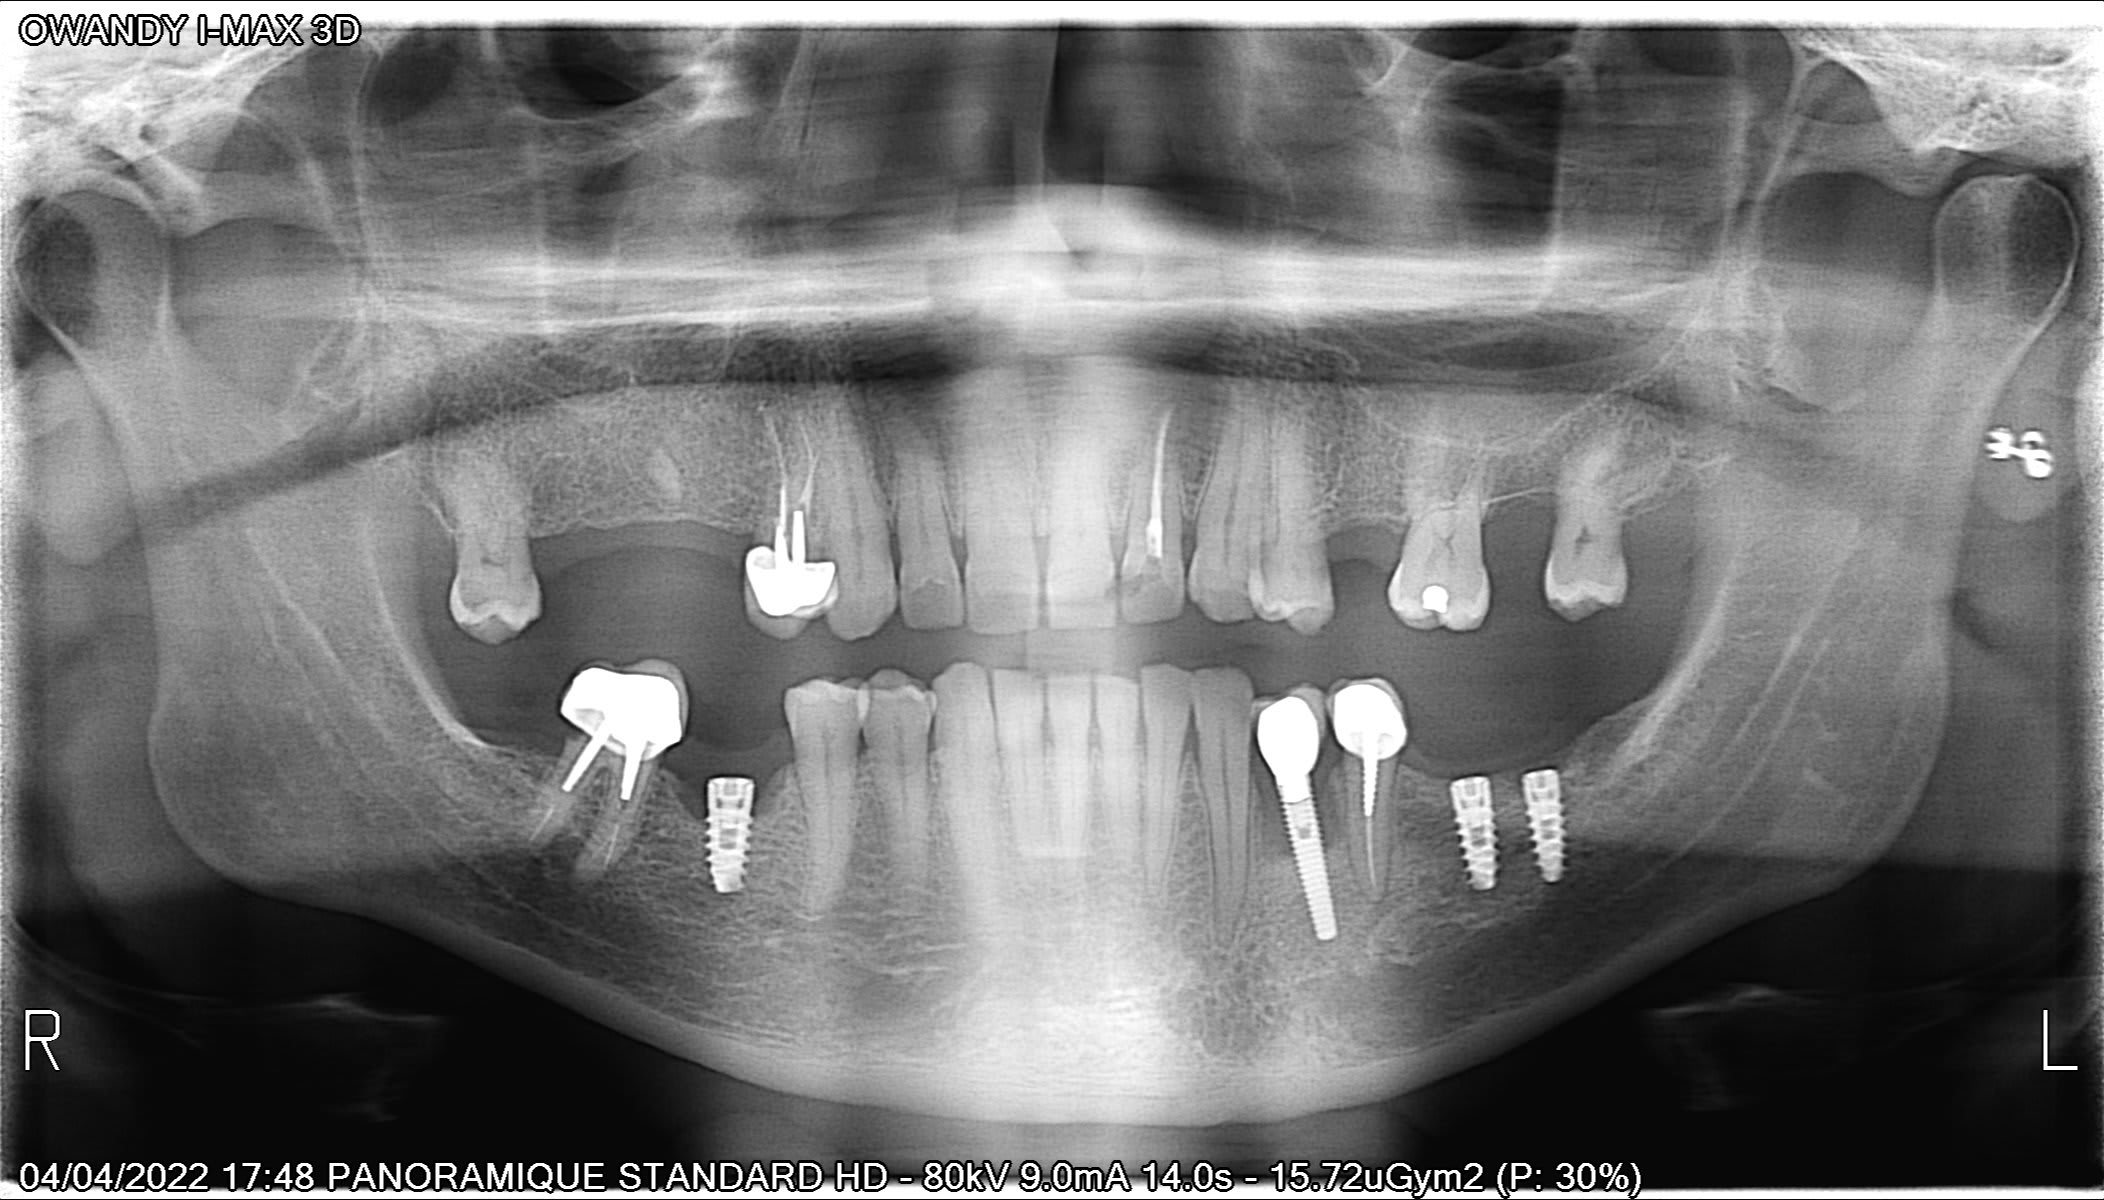

Bonjour, si quelqu'un peut m'aider a retrouver le système utiliser.

MIS seven aussi....

https://www.spotimplant.com/fr/implants-dentaire/mis/seven-2